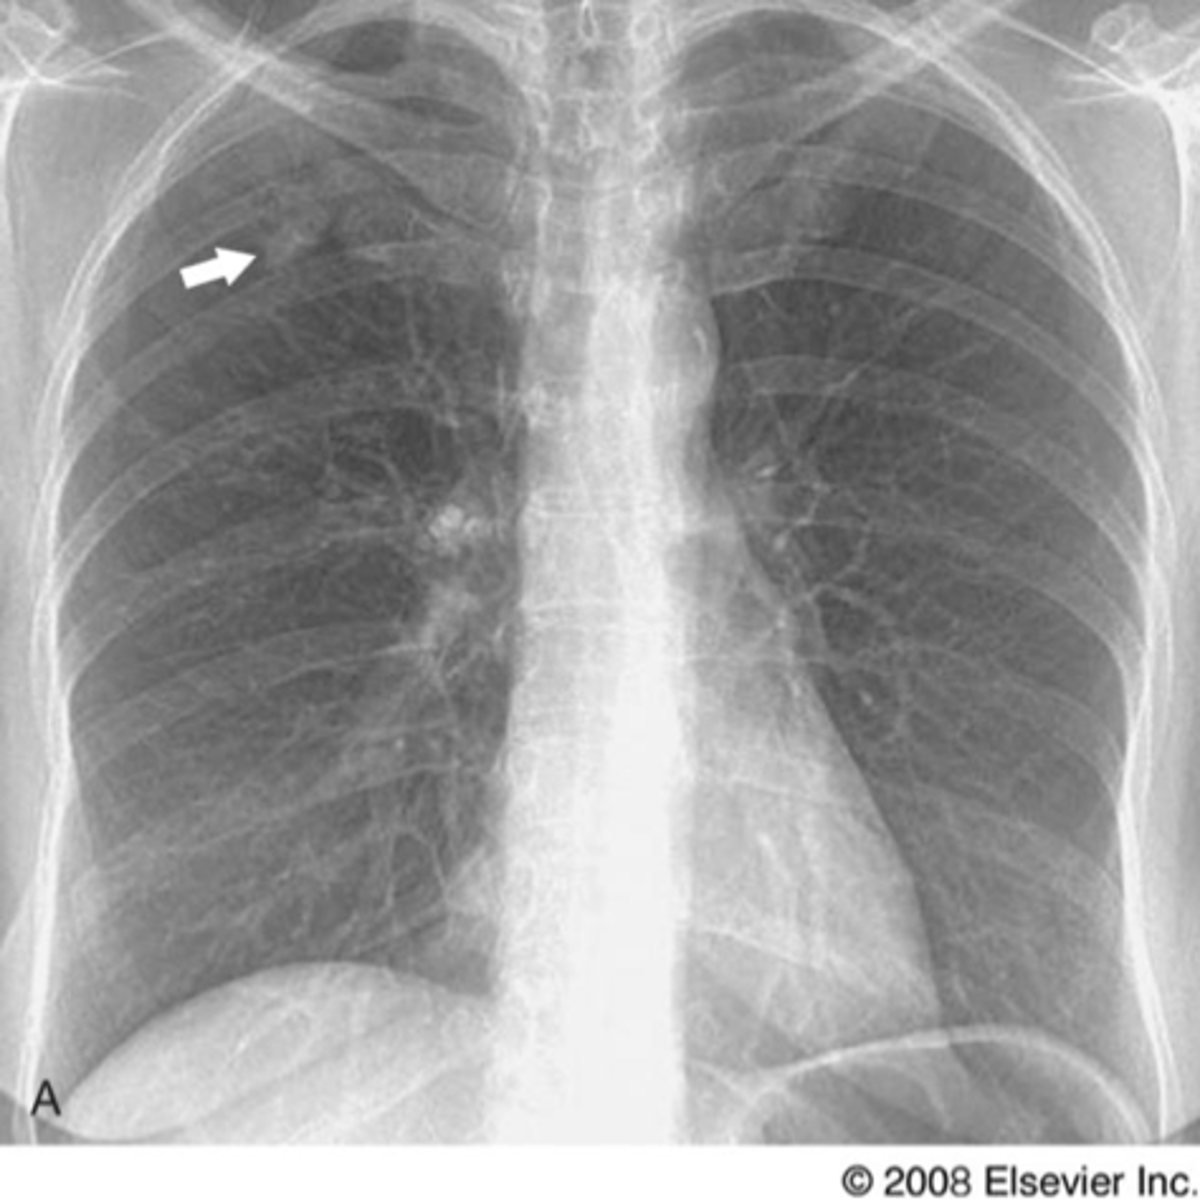

Solitary pulmonary nodule

Nodule